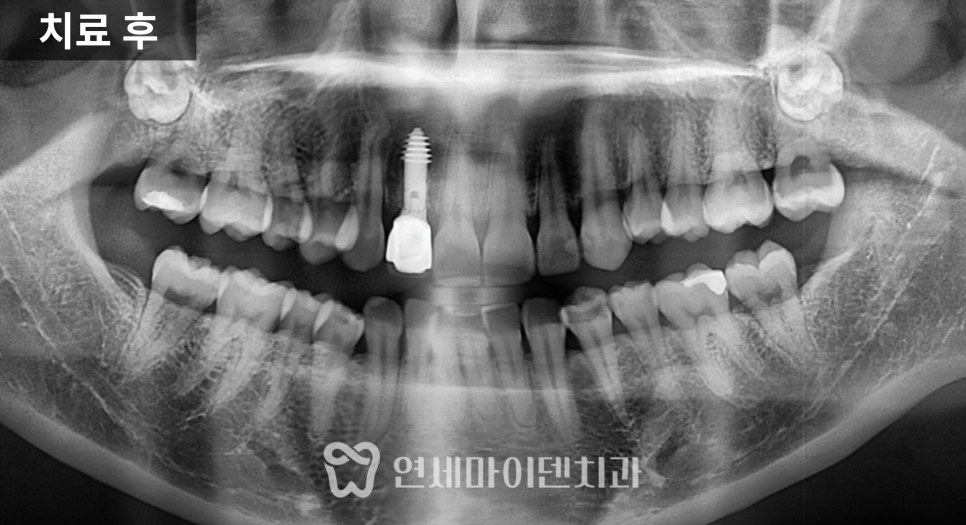

경과 관찰 후 보철 연결

수술 후에는 잇몸 회복 상태를

지속적으로 확인했습니다.

염증의 원인이 제거되면

잇몸은 비교적 빠르게 안정되는 경우가 많습니다.

3개월의 치유 기간을 거친 뒤

상부 구조를 연결하고

맞춤형 지대주를 형성한 후

보철을 완성했습니다.

이 시점부터 해당 부위로 식사가 가능해졌고

환자분의 생활 불편이 크게 줄었습니다.

2차 치료: 반대편 회복

시간이 지나면서

반대편도 불편감이 증가해

추가 치료를 진행하게 되었습니다.

위쪽 2개, 아래쪽 2개

4개의 임플란트를 계획했습니다.

발치 후 내부를 확인하니

오랜 기간 축적된 세균막이 관찰되었습니다.

이러한 세균막은

치주질환을 악화시키는 원인이 되기 때문에

초기 정리가 매우 중요합니다.

이후 잇몸 회복을 확인하면서

보철까지 마무리했고

양쪽 어금니로 균형 있게

식사가 가능한 상태를 목표로 치료를 진행했습니다.